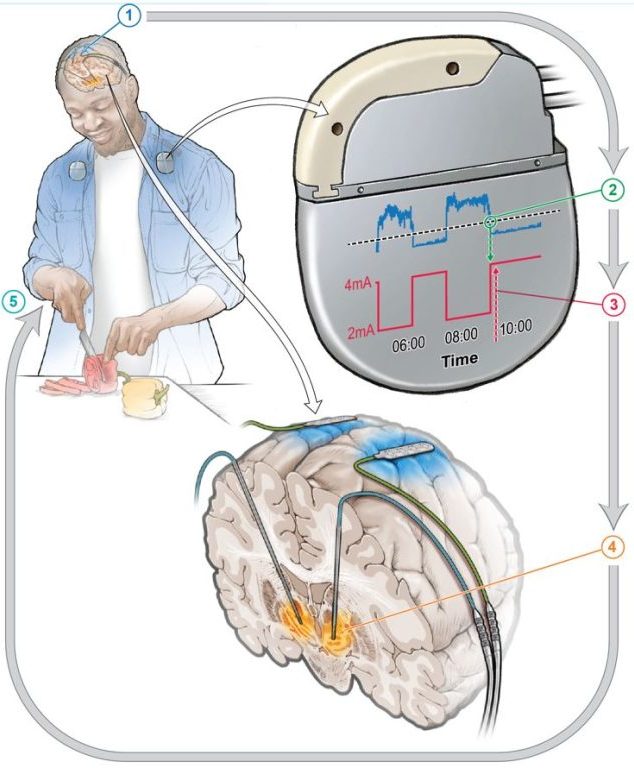

در این درمان، از یک دستگاه قرار گرفته در بدن استفاده شده که توسط فعالیت مغز بیمار هدایت میشود. این رویکرد میتواند روشی پایدار و پیشرفته برای درمان مبتلایان به بیماری پارکینسون (PD) ارائه دهد.

سیستم حلقه بسته برای درمان بیماری پارکینسون

تحریک عمیق مغزی تطبیقی که با عنوان سیستم حلقه بسته نیز شناخته میشود، تلاش میکند تا یک تکنیک موجود که برای درمان بیماری پارکینسون و سایر اختلالات مغزی استفاده میشود را بهبود بخشد.

بهعبارت ساده، این تکنیک از یک دستگاه استفاده میکند که در بدن قرار میگیرد و با توجه به فعالیت مغز تنظیم میشود و درمانی مداوم و شخصیسازیشده ارائه میدهد که علائم را بهطور موثرتری نسبت به تحریک عمیق مغزی معمولی بهبود میبخشد.

در این مطالعه، ابتدا چهار بیمار درمان مرسوم تحریک عمیق مغزی را دریافت کردند و سپس تحت درمان تحریک عمیق مغزی تطبیقی همراه با تحریک عمیق مغزی قرار گرفتند.

دانشمندان از هوش مصنوعی (AI) برای آموزش مدل تحریک عمیق مغزی تطبیقی استفاده کردند. این مدل که عمدتاً زیرمجموعهای از هوش مصنوعی است، به تجزیه و تحلیل و یادگیری از الگوهای فعالیت مغزی شرکتکنندگان کمک میکند.

این الگوریتم به دستگاه تحریک عمیق مغزی تطبیقی اجازه میدهد تا سیگنالهای مغزی مرتبط با علائم پارکینسون را شناسایی کرده و سطح تحریک الکتریکی را در زمان واقعی کالیبره کند. این کالیبراسیون بدون وقفه به دانشمندان امکان میدهد تا علائم پارکینسون را بهتر مدیریت کنند.

هوش مصنوعی با پالایش مداوم پاسخها بر اساس دادههای دریافتی از مغز، از یک رویکرد سفارشی برای نیازهای بیمار اطمینان استفاده میکند. این رویکرد، قابلیت تحریک عمیق مغزی تطبیقی را از تحریک عمیق مغزی سنتی متمایز میکند که بهطور خودکار بر اساس فعالیت مغز در زمان واقعی (آنلاین) تنظیم نمیشود.

طبق گفته دانشمندان، در یک مطالعه قبلی توانایی این درمان برای ثبت فعالیت مغزی در افراد در حین انجام کارهای روزمره خود شرح داده شده بود. با این حال، برای اطمینان از تناسب درمان شخصیسازیشده برای افرادی که از پارکینسون رنج میبرند، هنوز نیاز به تنظیمات دقیقتر پیش از افزایش مقیاس دستگاه وجود دارد.